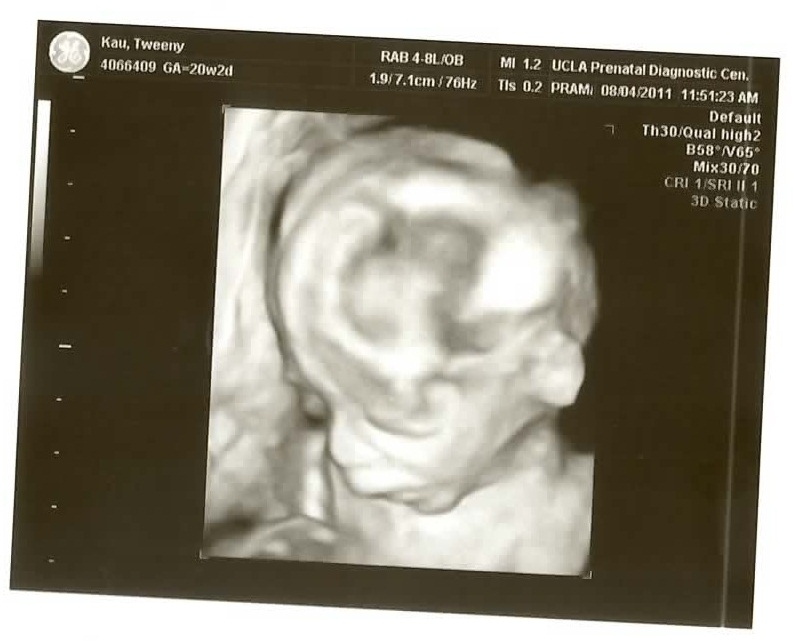

We just went back for our twenty week checkup/ultrasound and as usual they gave us a DVD which I have ripped to YouTube (it’s just everything they did.. 17:10 long.. I cut out the first 2:20 of the intern bumbling around to keep it under the 15 minute YouTube maximum).

See if you can figure out what gender it is from the ultrasound pics! Check the comments for the answer!

The 3D pictures are kind of funny because the ultrasound technicians are all like “So CUTE!” and all I can think is “for a pig face!” The one face-on isn’t so bad if you don’t look above the bottom lip I guess..